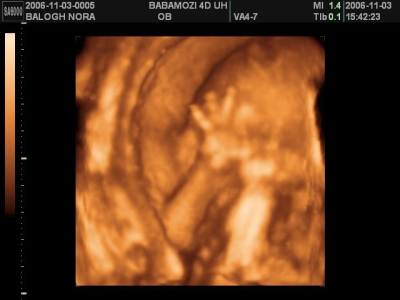

Egyébként egy vizsgálat úgy kezdődik, hogy megkérdezi, hogy "Hogy vagyunk, minden rendben?" Ha igen, akkor UH, kép. És amikor leülsz az asztalhoz, elmondja, mit írt a kiskönyvbe. Mik a pontos adatok. 100szor UH-zott, mégis mindig szól, hogy "jaj, ez most hideg lesz" meg ilyesmi. Én úgy gondolom, hogy egy probléma mentes terhesség során nem is kell, hogy tovább tartson egy vizsgálat.